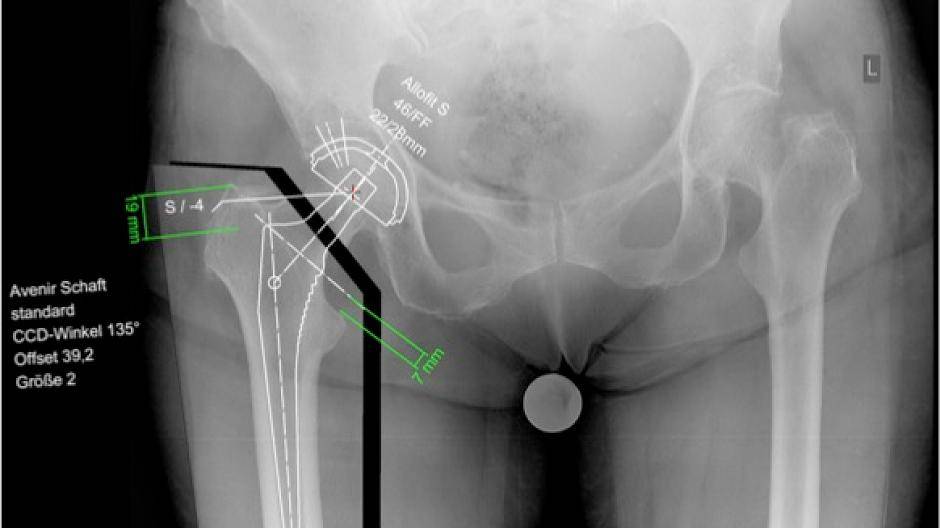

Fotos Unfallchirurgie und Orthopädie